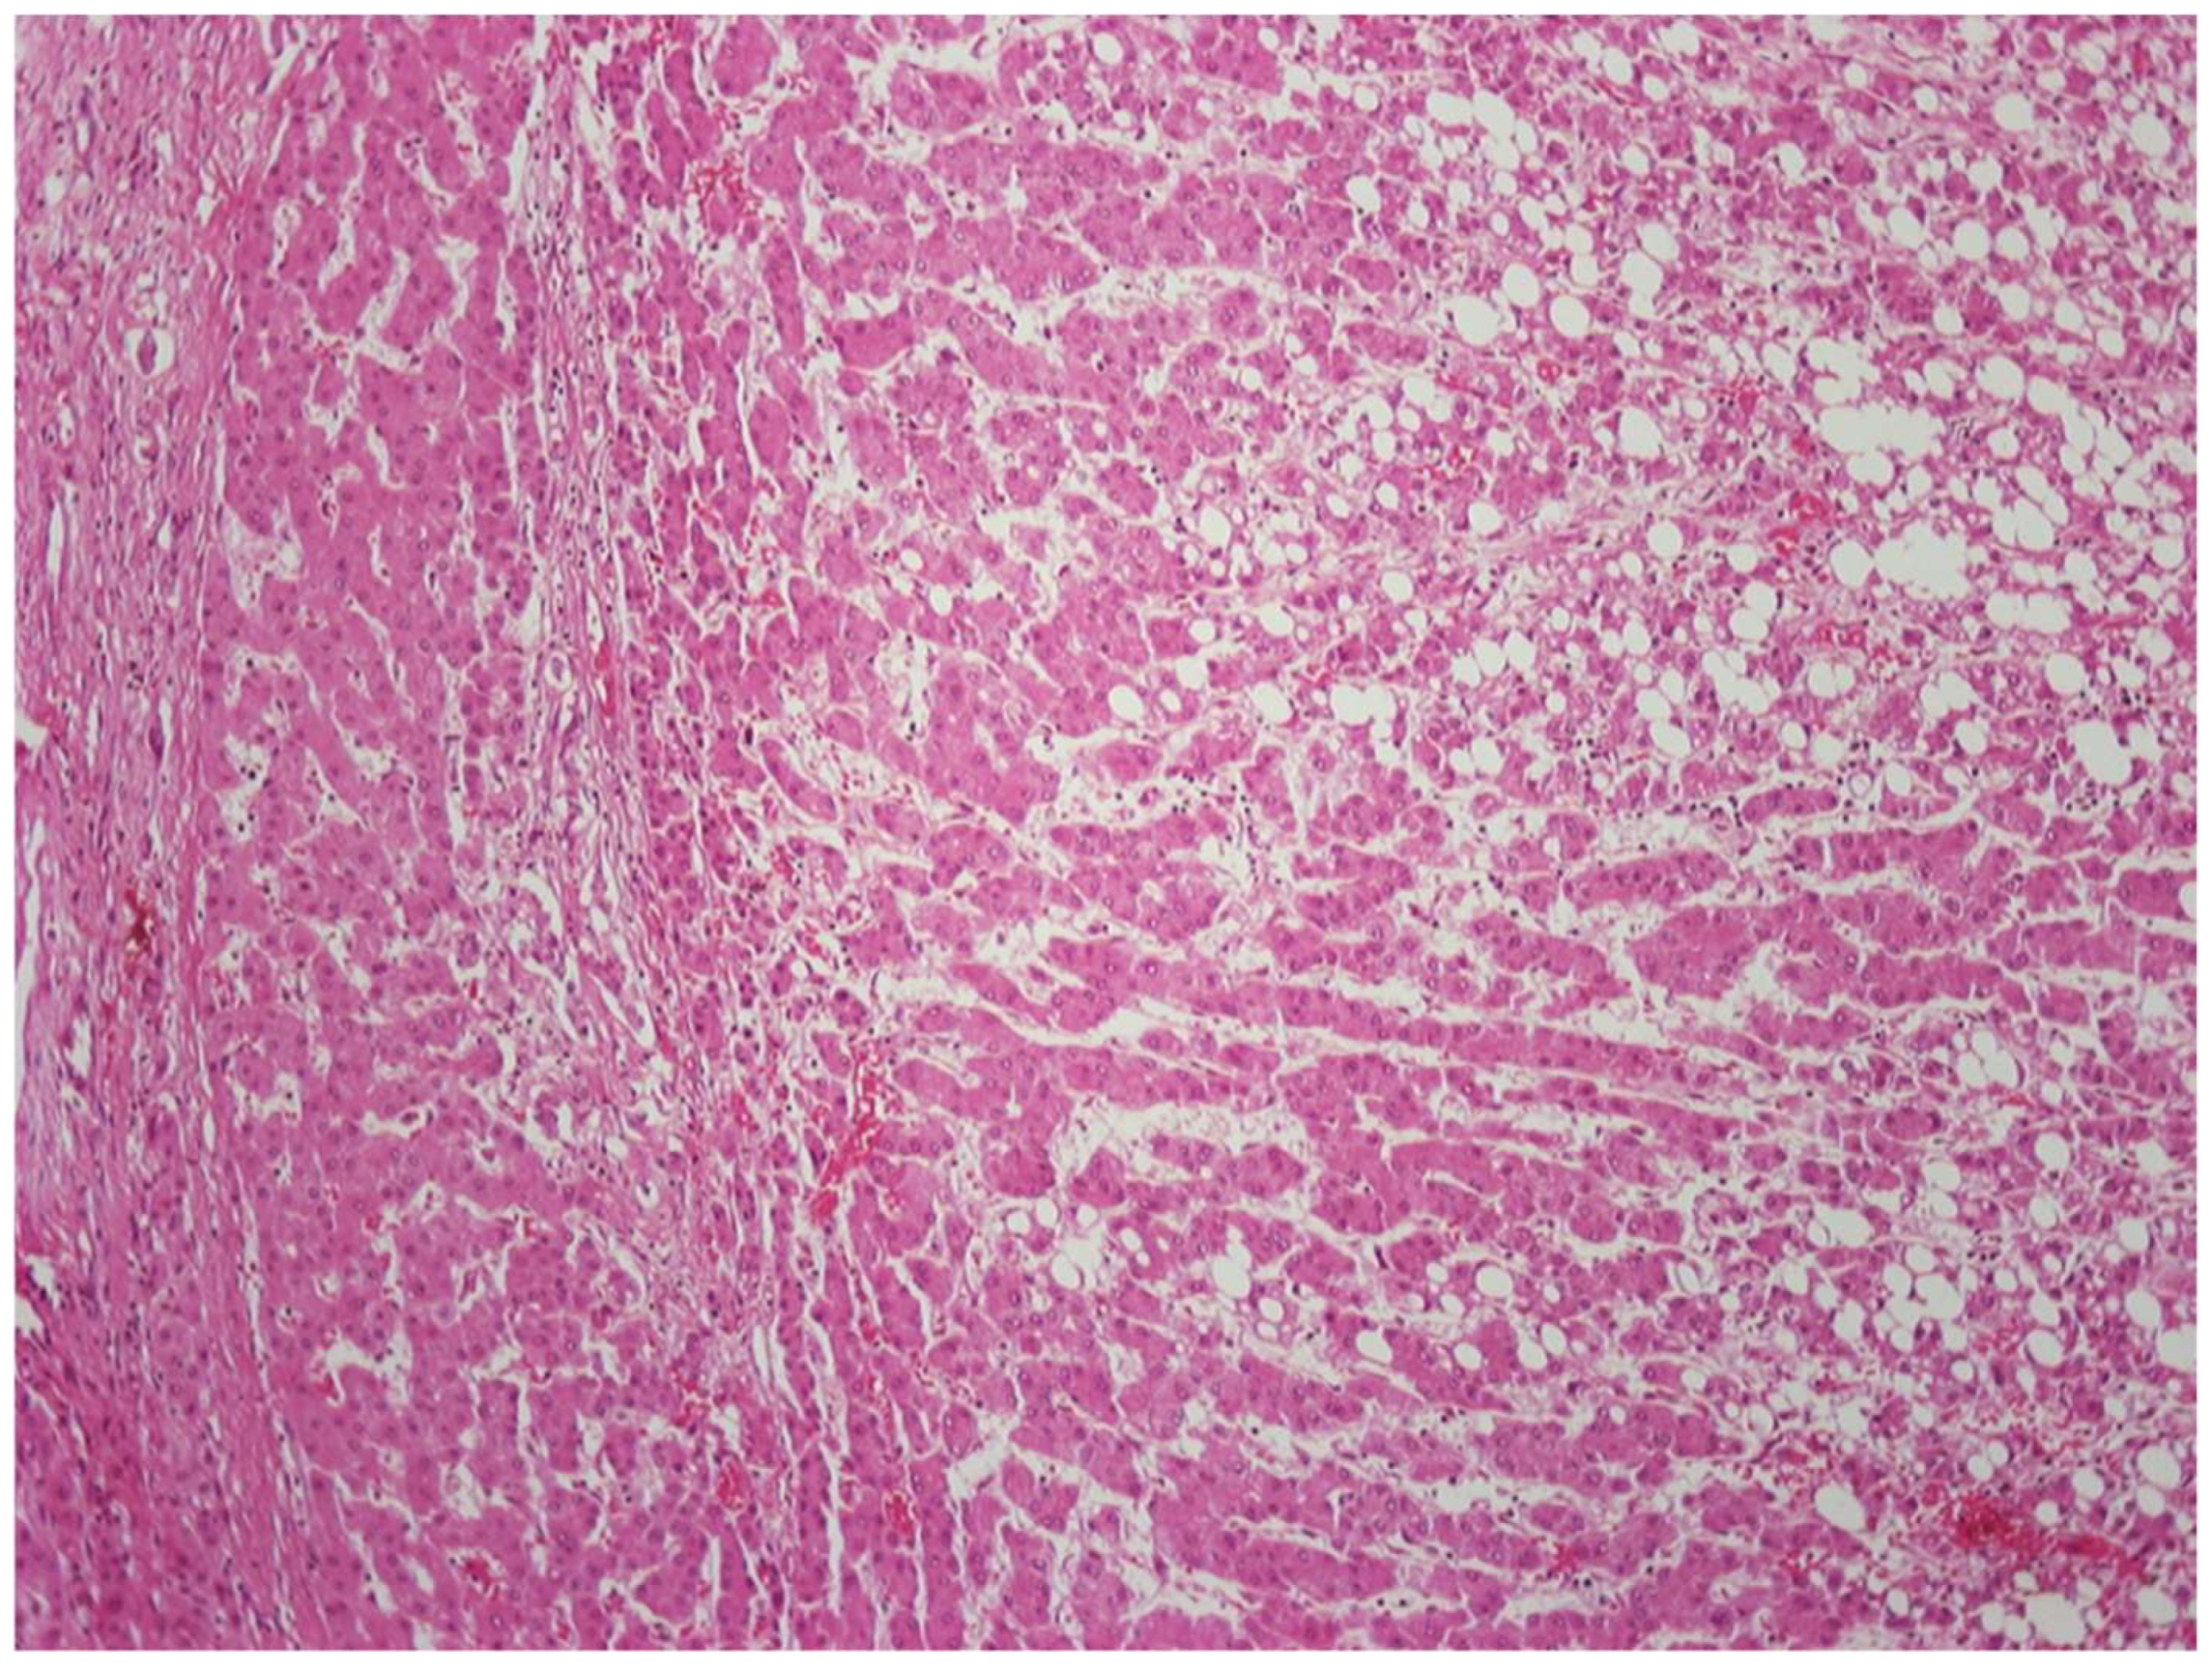

| Steatohepatitic | Features simulating steatohepatitis (macrovesicular steatosis, inflammation, ballooned cells, Mallory–Denk bodies, and pericellular fibrosis) | IL6/JAK/STAT pathway activation |